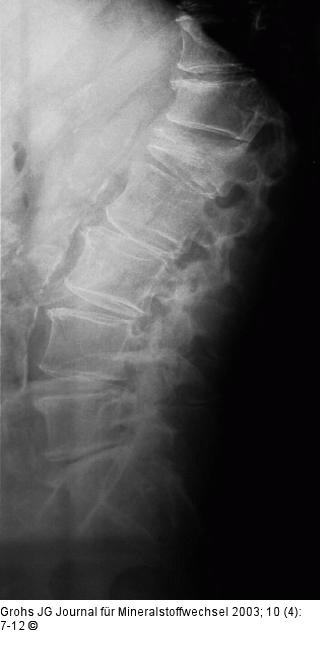

Abbildung 1: Osteoporotische Wirbelkörperfraktur Typische osteoporotische Wirbelkörperfraktur L1 (geringer auch Th12) mit keilförmiger Deformität und Verminderung der Wirbelkörperhöhe. |

Abbildung 1: Osteoporotische Wirbelkörperfraktur

Typische osteoporotische Wirbelkörperfraktur L1 (geringer auch Th12) mit keilförmiger Deformität und Verminderung der Wirbelkörperhöhe. |